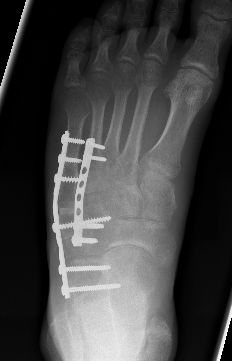

ORIF

ORIF +/- bone grafting

Screw fixation if simple fracture

Cuboid plates

Cuboid platesynthes cuboid

Bridge plating

Severe comminution / lateral column shortening

- consider temporary distractor / external fixation to obtain length

- calcaneum to 4th / 5th metatarsal plate

- non-weight bearing until union then remove plates (typically 12 weeks)